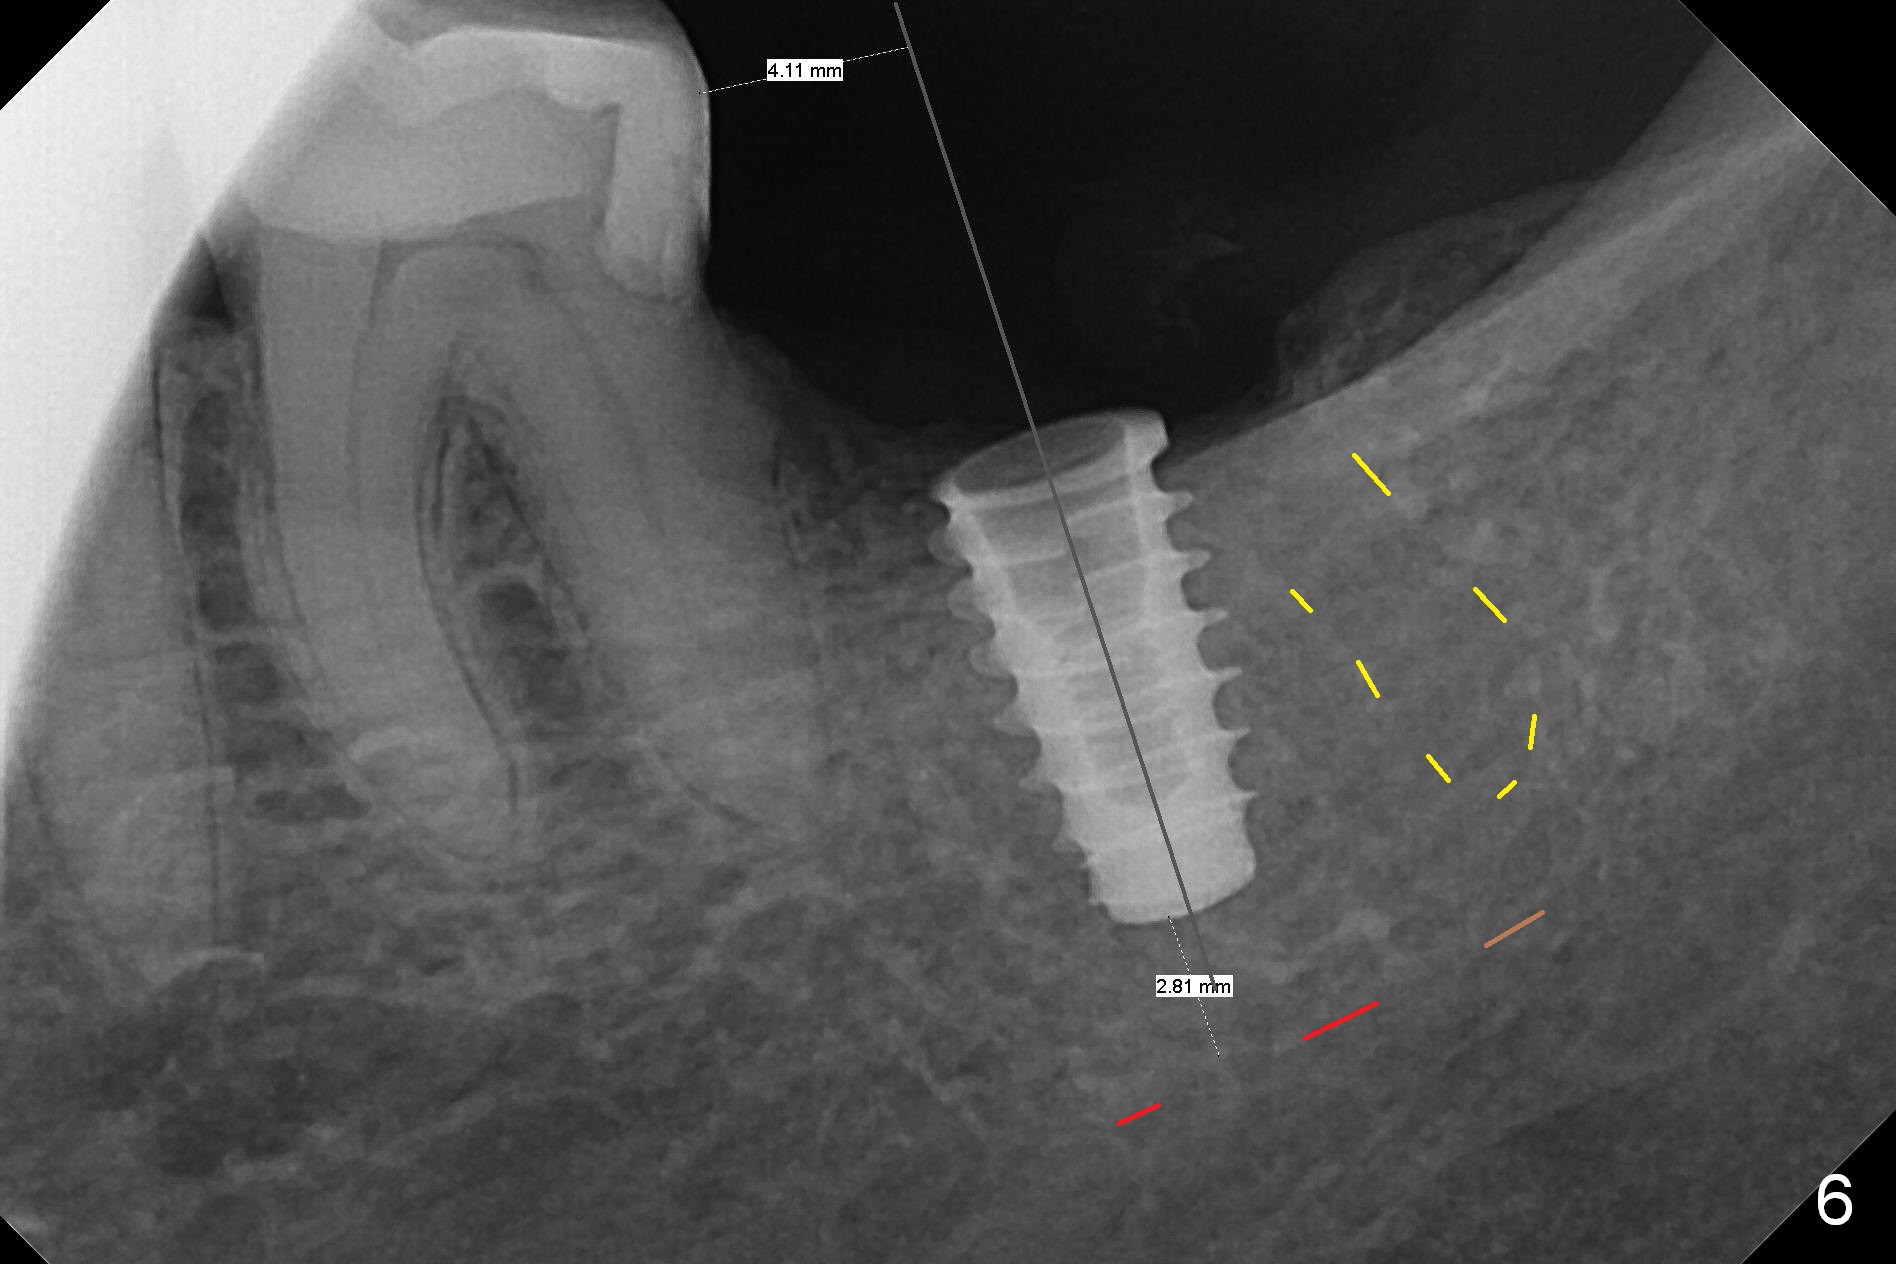

Preop palpation of the edentulous area at #18 does not show the flatness of the ridge top as shown by CBCT.  Incision reveals that the ridge is not as wide as CBCT indicates (Fig.1 (coronal section) between arrowheads).  In fact the ridge is concave (Fig.2 red dashed line).  Osteotomy is initiated in the middle of the concavity (Fig.2 green line) with insertion of 7 mm guide pin (Fig.3).   After removal of the pin, the osteotomy is moved buccally (Fig.4).  After Marking Bur and 4.3 mm Magic Drill, a 5x9 mm IBS implant is placed with 2.8 mm clearance from the Inferior Alveolar Canal (Fig.6).  Following deepening the osteotomy with Final Drill, the implant is placed deeper (Fig.7).  The osteotomy happens to be established in the mesial socket, since the distal socket has not completely healed (Fig.6 yellow dashed line).  Granulation tissue is removed.  Since the lingual crest is lower than the buccal one (Fig.1 B), there is lingual thread exposure after implant placement (Fig.5).  The exposed thread is covered by bone graft (autogenous bone, allograft and Osteogen, Fig.5 pink circles).  Some of the graft is apparently pushed into the distal socket (Fig.7 yellow dashed line) post GBR and suture.  As the implant is placed twice, insertion torque is <10 Ncm (although the implant is stable).  A 5x3 mm healing abutment is placed (Fig.7 H).